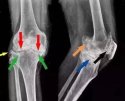

下颌骨骨折包括上颌骨折和下颌骨骨折;根据骨折创伤是否暴露,可分为开放性骨折和闭合性骨折。